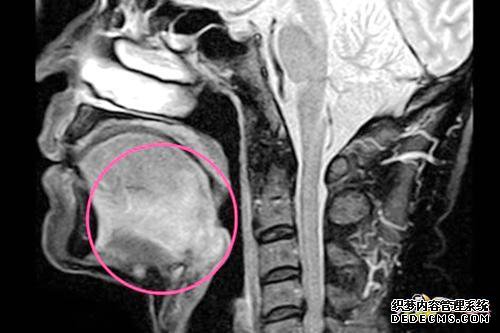

口咽癌的最初症状

因为口咽的位置相对较晚且较深,所以最初的症状相对较轻,任何人都容易忽略,主要是由于异物或咽部不适和感觉引起的是的。

如果肿瘤生长或破裂,可能会引起喉咙痛,尤其是在吞咽期间,并且喉咙痛可能会增加或唾液中可能有血液。

此外,如果出现异常口臭,这是由于吞咽神经受累所致,但这是错误的,但这必须是由舌咽反射引起的,从而导致耳朵前部和另一端在基座上的疼痛有这种舌根癌,有反射性的面部疼痛。

一旦肿瘤发展到一定程度,张口就会受到一些限制,甚至可能会出现疼痛恶化。